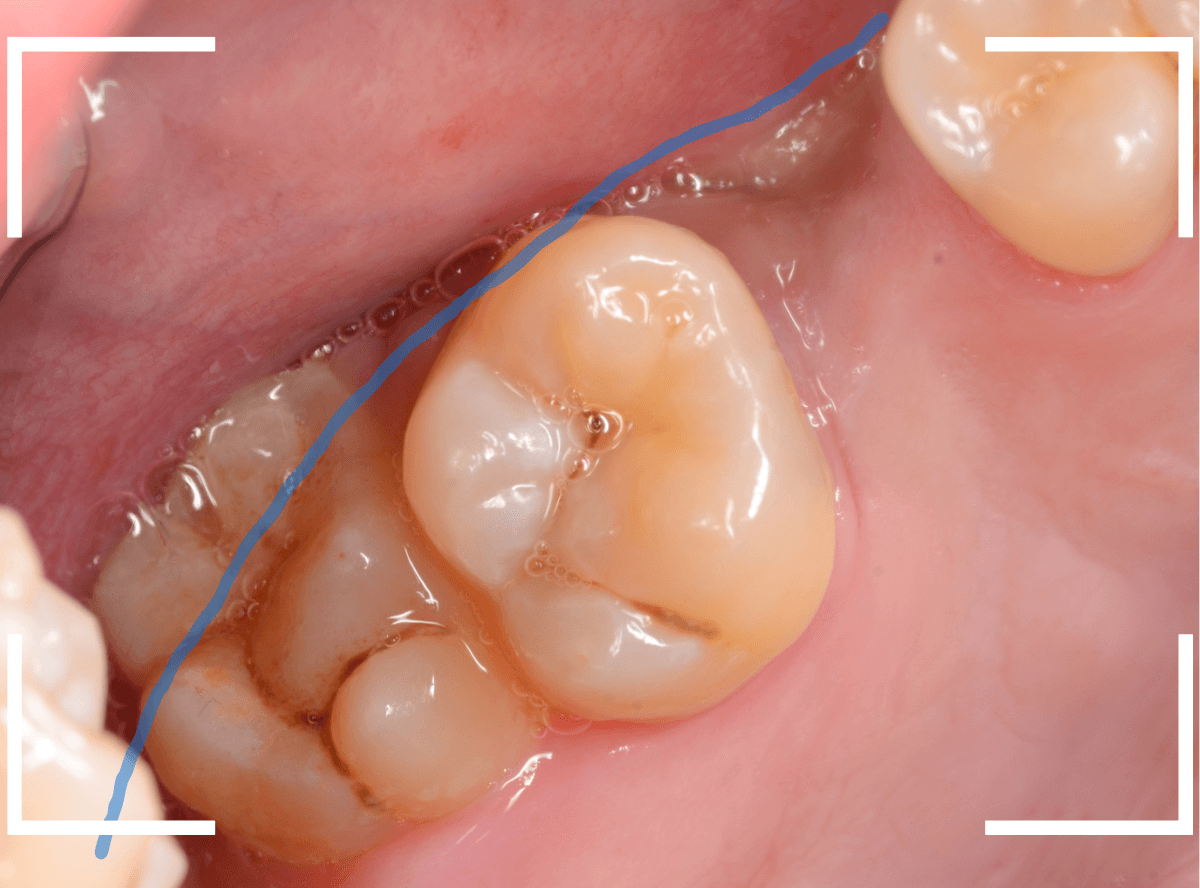

抜歯後に長期間お痛みが出たり、経過観察が必要な難しいおやしらずの抜歯ならまだしも、簡単なおやしらずの抜歯を避けてしまったがために、他の歯に悪影響を与えてしまったもったいない例も多々見てきました。

ここでは、比較的簡単なおやしらずの抜歯の例を中心にご紹介します。

このようなおやしらず、あなたはありませんか?